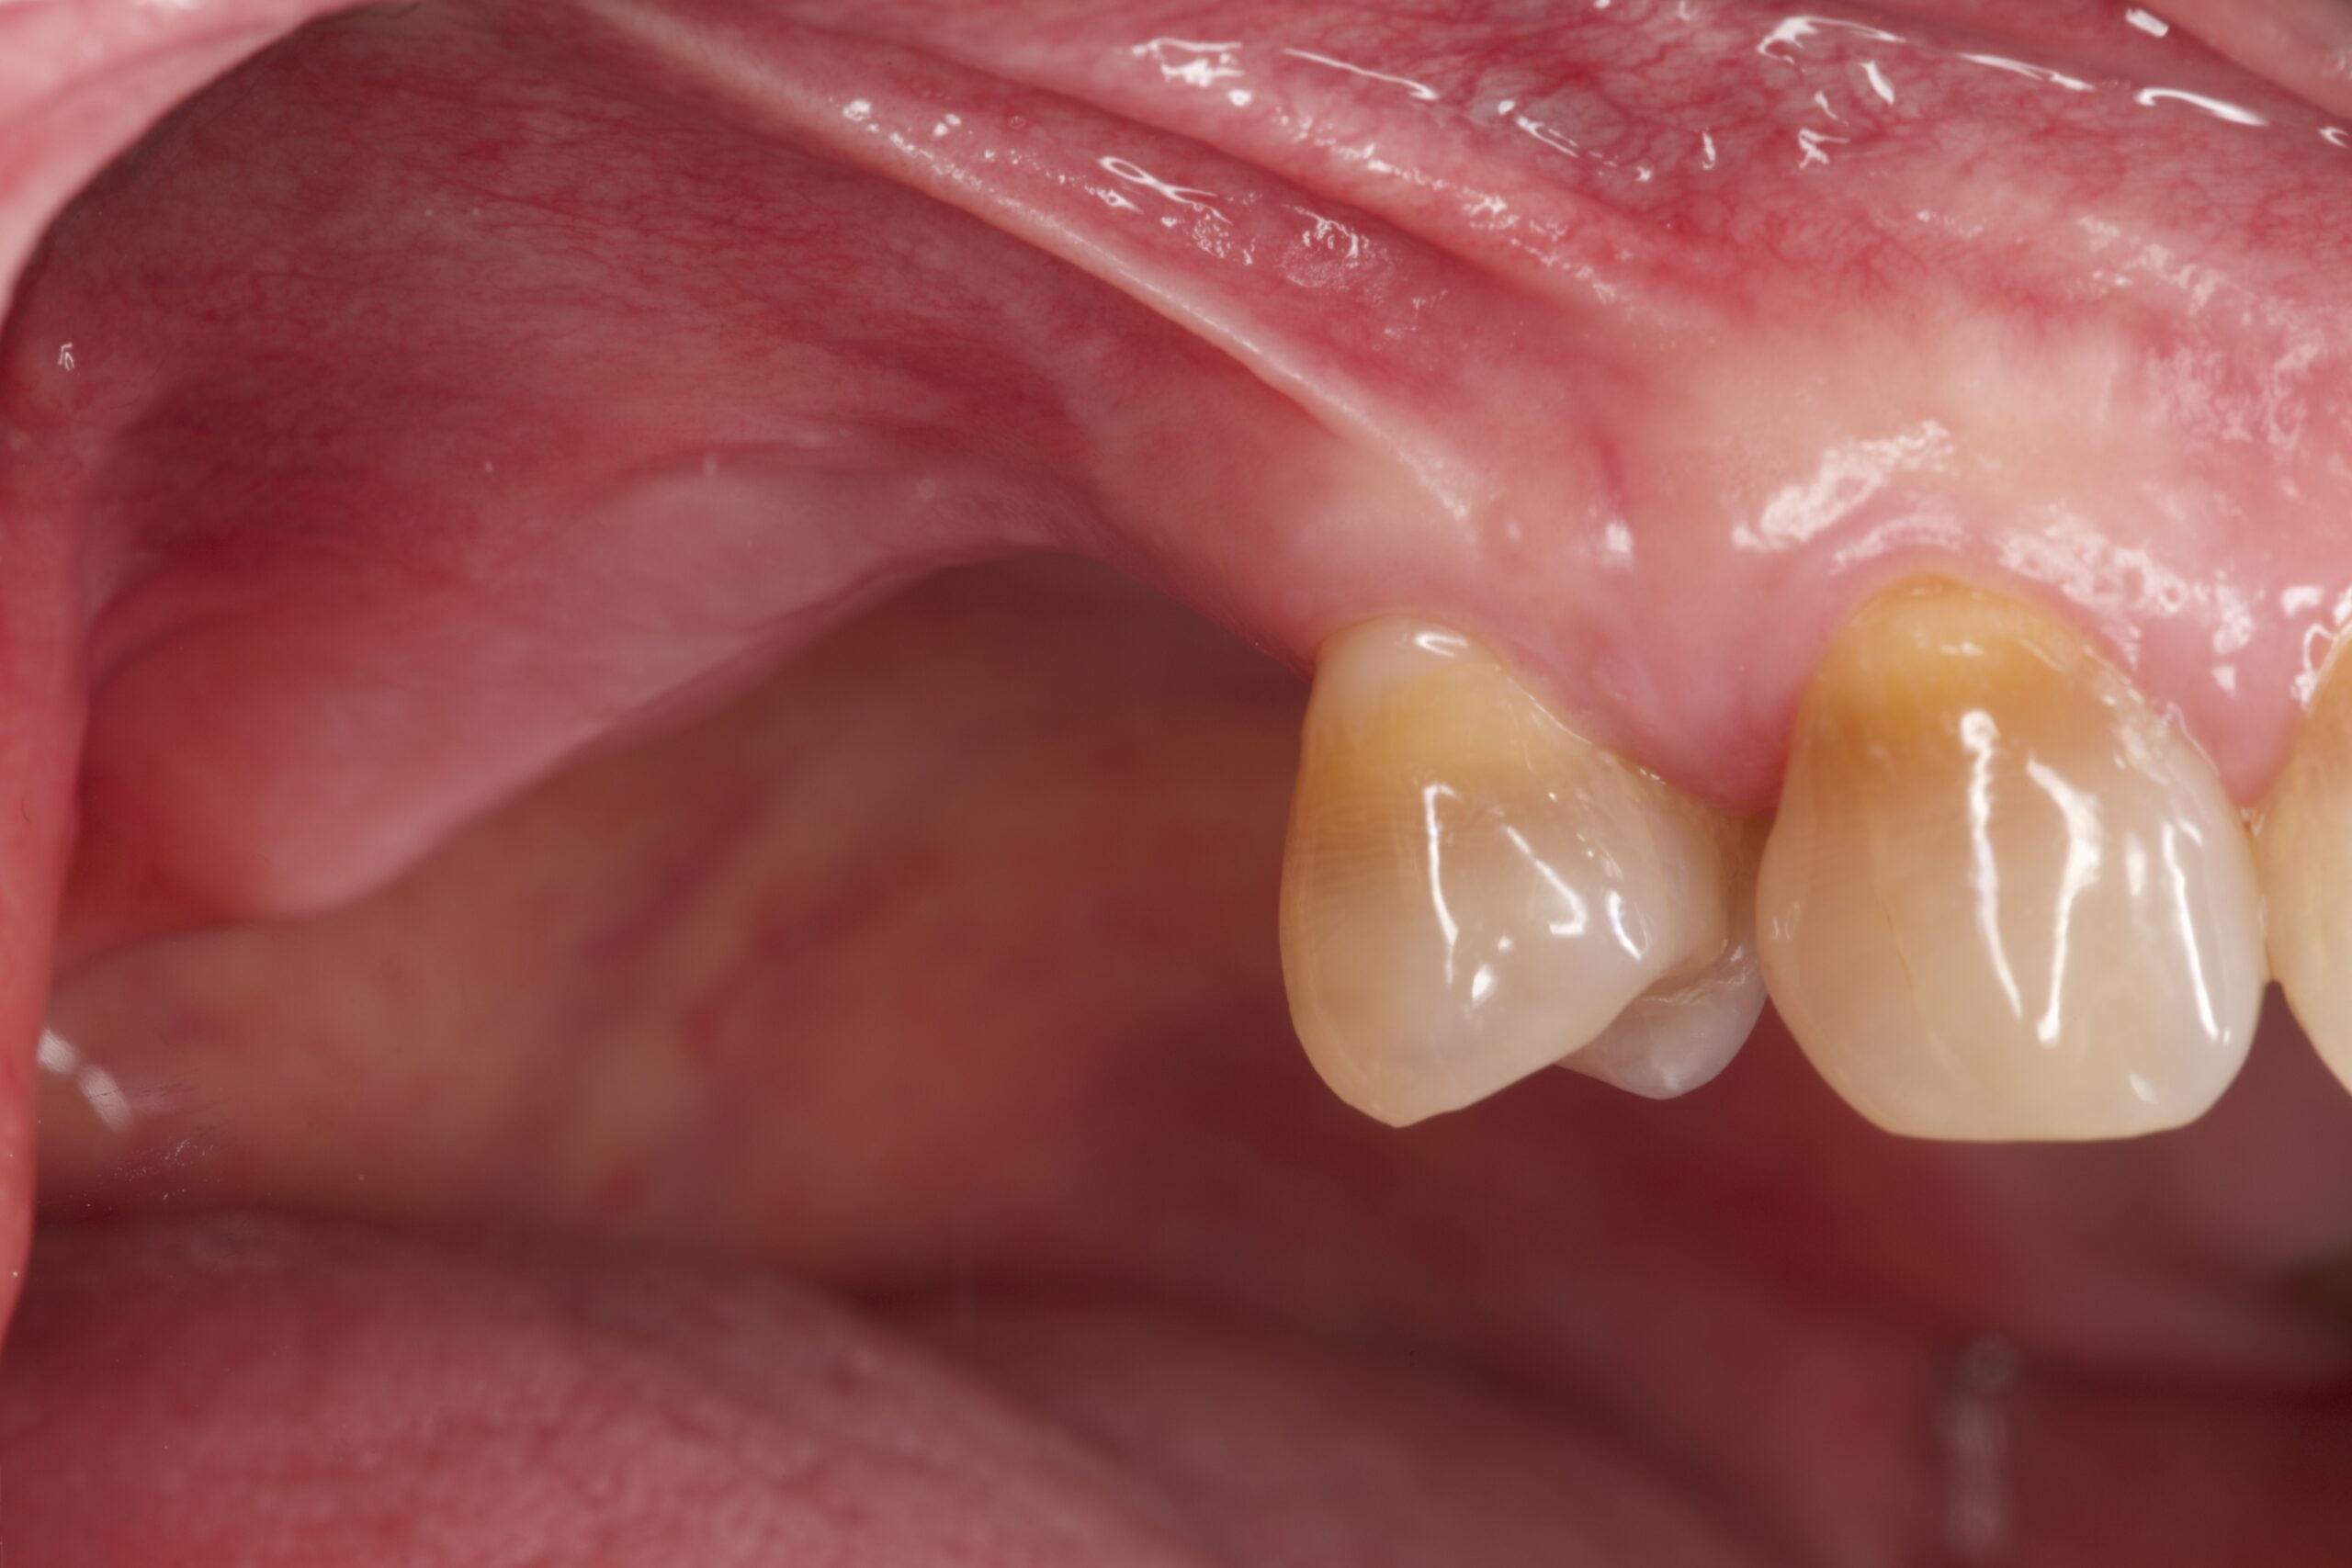

下顎の歯肉退縮が気になるとのことで来院されました。 年齢や、歯ブラシの仕方、元々の歯肉の薄さなどが原因で、歯ぐきが下がってしまいました。 上顎から歯肉を採取し、下がった歯ぐきに移植を行い、元の状態に回復することができまし […]